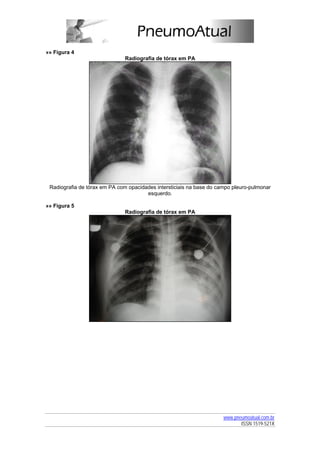

»» Figura 5

Radiografia de tórax em PA

Radiografia de tórax em PA de paciente com pneumonia estafilocócica mostrando opacidades

alveolares bilaterais, mais extensas na metade inferior do campo pleuropulmonar esquerdo.

Nota-se a presença de cavidades também bilateralmente. A tomografia computadorizada de

tórax (janela de pulmão) mostra com maiores detalhes os múltiplos focos de consolidação,

alguns deles com cavitação. Embora não seja a janela ideal, as opacidades localizadas

bilateralmente nas porções dorsais sugerem a presença de derrame pleural.